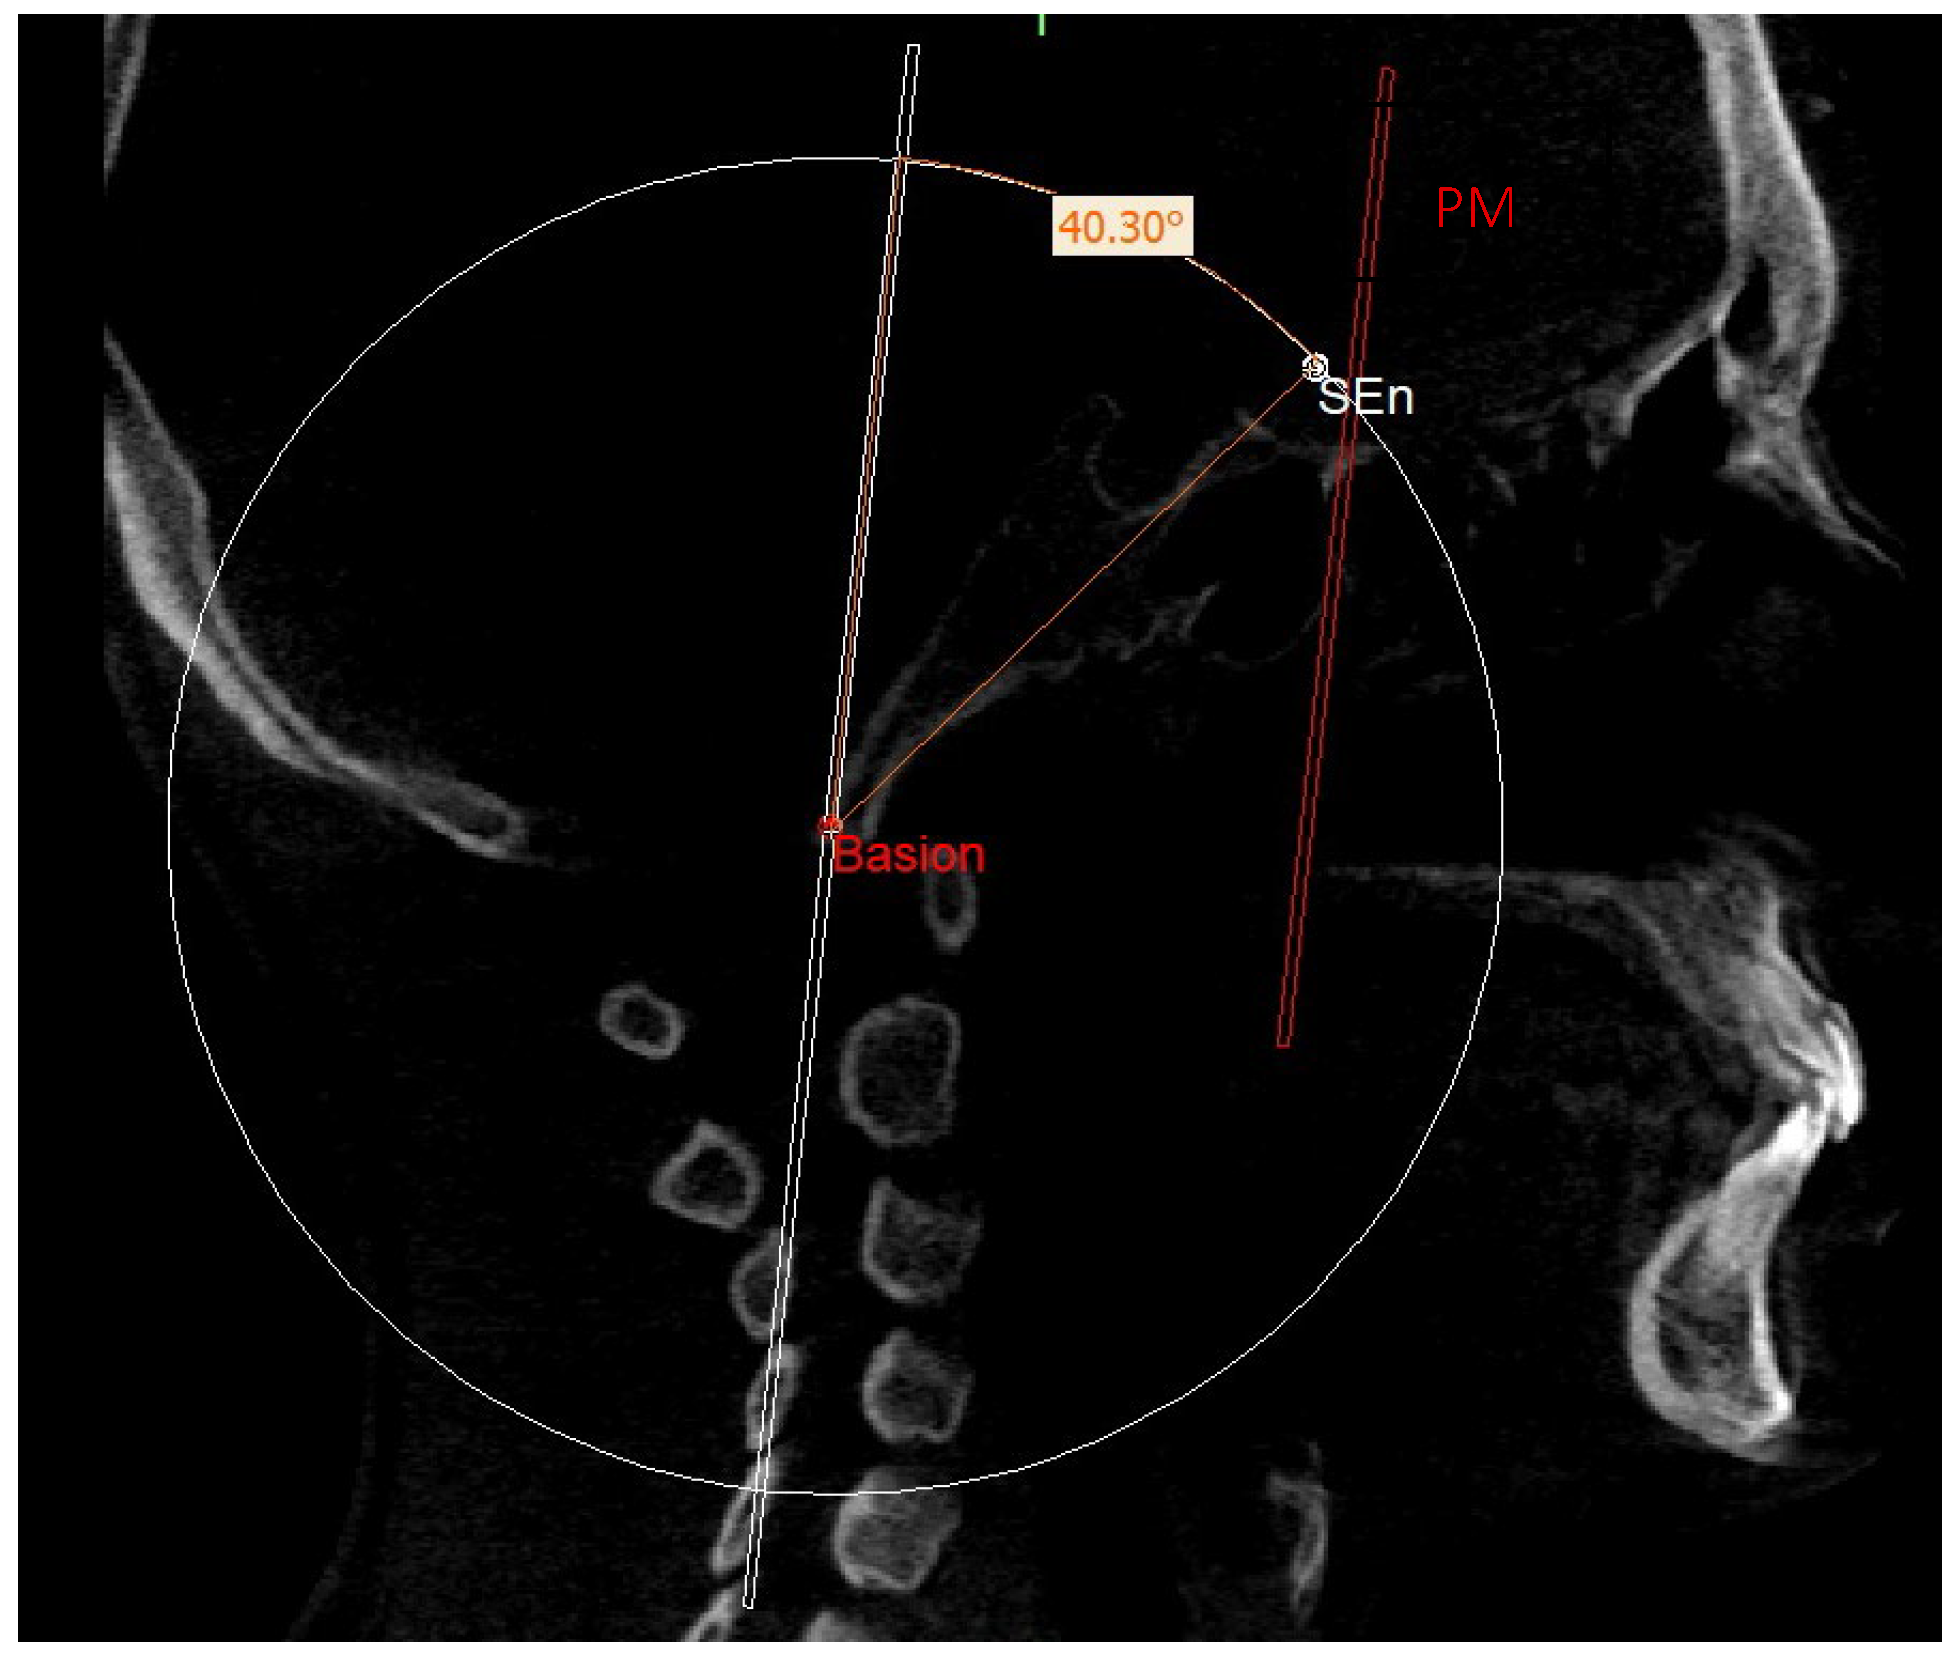

| SEn | SE neutral: the point of a circumference with the center in Ar and the radius equal to the MCF, in which an angle of the skull base equal to 40.3° is obtained |

| PMn | PM neutral: the line parallel to the PM forming at the point SEn an ideal angle of 40.3° with the MCFn |

| MCFn | MCF neutral, Ar—Sen |

| SE neutral (SEn) | / | Point of a circumference with center in Ba and radius equal to MCFx, in which an angle of the skull base equal to 40.3° is obtained | / |

| MCF neutral (MCFn) | Plane passing through the Ba, rSEn and lSEn which forms an angle of 40.3° with the PMn at the SEn point |

| PM neutral (PMn) | Plane parallel to the PM such as to form an ideal angle of 40.3° with the MCFn at the SEn point |